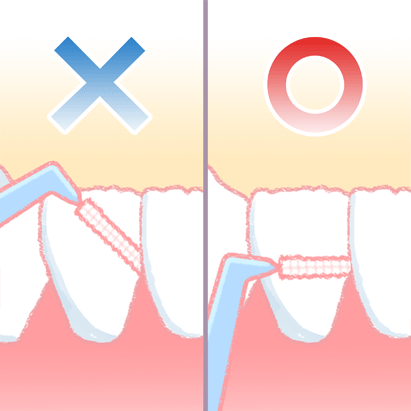

⑥ 前回詰めた綿花の状態を確認して、良い状態なら、「根管充填剤」(マスターポイント・アクセサリーポイント)というお薬を、余分な空間がないように根っこに詰めます。

⑥ 前回詰めた綿花の状態を確認して、良い状態なら、「根管充填剤」(マスターポイント・アクセサリーポイント)というお薬を、余分な空間がないように根っこに詰めます。 Q1.痛みはありますか?

Q1.痛みはありますか? ② 次に、「根管長測定器」という機械を使い、根っこの長さを正確に測ります。

② 次に、「根管長測定器」という機械を使い、根っこの長さを正確に測ります。

⑤ 次に、仮詰めをします。

⑤ 次に、仮詰めをします。 虫歯が神経まで達して炎症を起こしているので、人によってはズキズキとした痛みを感じる方もいます(>_<)

虫歯が神経まで達して炎症を起こしているので、人によってはズキズキとした痛みを感じる方もいます(>_<)